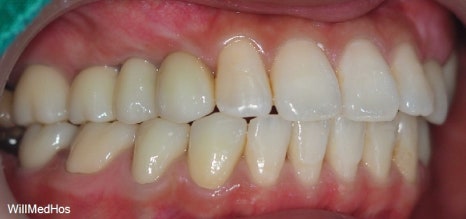

위의 사진이 최종 치료 사진 입니다. 뼈이식, 신경치료 후 크라운, 임플란트 치료를 진행 하였고

최종 기간은 10개월 정도 소요 되었습니다.

▲ 최종 완료 구강 사진